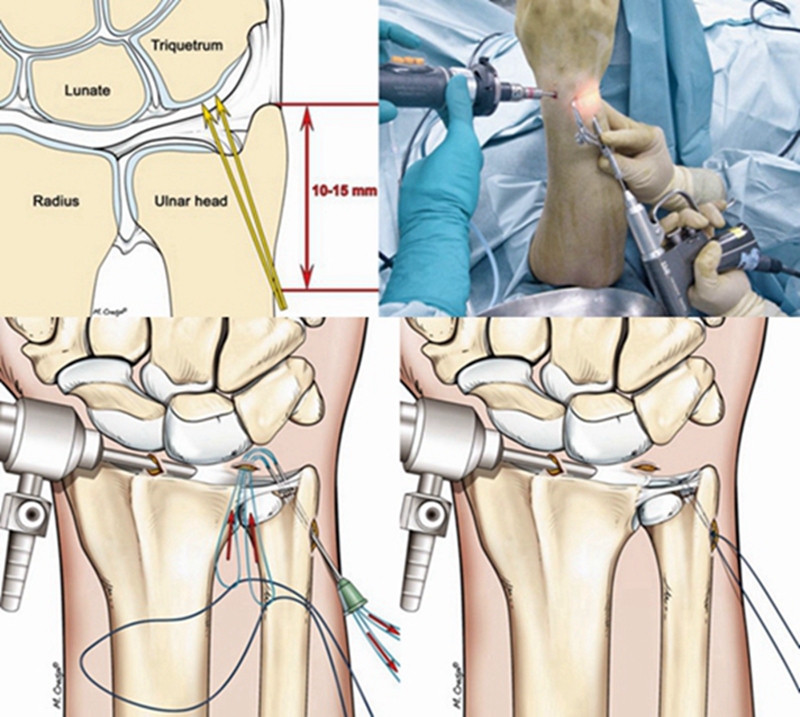

TFCCⅡ型损伤,对症状持续存在,经保守治疗无效者可行腕关节镜手术。

ⅡA、ⅡB、Ⅱc型损伤:腕关节镜下清创术及软骨成形术;若合并尺骨撞击或尺骨正变异者,行关节镜下清创术结合尺骨头部分磨除术(Wafer术)。